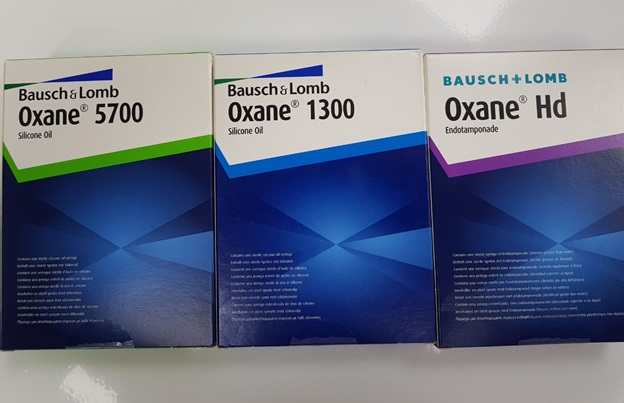

Unfortunately, retinal glue has not yet been invented, but the laser turned out to be very effective. The laser “welds” the retina to the underlying tissues along the edges of all the breaks. After the application of laser coagulates, local inflammation occurs, and then a microtubule is gradually formed (5-7 days) on the choroid. Therefore, it makes sense to leave “heavy water” in the eye for a week. In some cases, this is enough to keep the retina in place, but it may be necessary to continue to hold the retina to form more durable adhesions. In such cases, silicone oil is used, which fill the eye cavity.

不幸的是,视网膜胶尚未被发明,但是激光被证明是非常有效的。 激光沿着所有断裂的边缘将视网膜“焊接”到下面的组织。 施加激光凝结后,发生局部炎症,然后在脉络膜上逐渐形成微管(5-7天)。 因此,将“重水”放在眼中一周是有意义的。 在某些情况下,这足以将视网膜保持在适当的位置,但是可能有必要继续保持视网膜以形成更持久的粘连。 在这种情况下,将使用硅油填充眼Kong。

Silicone is a clear, viscous liquid, the tissues almost do not react to it, so you can leave it in the eye for much longer. Silicone is not so good straightens and presses the retina, but to keep the retina unfolded, it fits perfectly.

硅酮是一种透明的粘稠液体,组织几乎不会对其产生React,因此您可以将其留在眼中更长的时间。 硅胶不是很好拉直并按压视网膜,但要使视网膜保持展开状态,它会非常适合。

The eye filled with silicone almost immediately begins to see, the retina retains its anatomical position, its functions are restored, and the adhesions in the areas of laser coagulates become very durable over time. One of the features of silicone is a change in the optical characteristics of the eye to the plus side by 4–5 diopters. Usually silicone is in the eye for about 2-3 months, after which the retina no longer needs any “props” and can be safely removed. This is also an operation, but not as complicated and voluminous as the previous ones.

充满硅酮的眼睛几乎立即开始可见,视网膜保持其解剖位置,恢复其功能,并且随着时间的流逝,激光凝结区域的粘连变得非常持久。 硅树脂的特征之一是眼睛的光学特性向正侧变化了4–5屈光度。 通常,硅树脂会在眼睛中停留约2-3个月,此后,视网膜不再需要任何“道具”,并且可以安全地将其去除。 这也是一项操作,但不如先前的操作那么繁琐。

In some cases, changes in the internal eye structures are so pronounced that the only option today is to have at least residual vision, or to keep the eye as an organ — is the constant presence of silicone in the eye cavity. In these cases, silicone can remain in the eye for many years, even decades.

在某些情况下,内部眼部结构的变化如此明显,以至于当今唯一的选择是至少具有残留的视力,或保持眼睛为器官-眼腔中不断存在有机硅。 在这些情况下,有机硅可以在眼睛中保留很多年,甚至数十年。